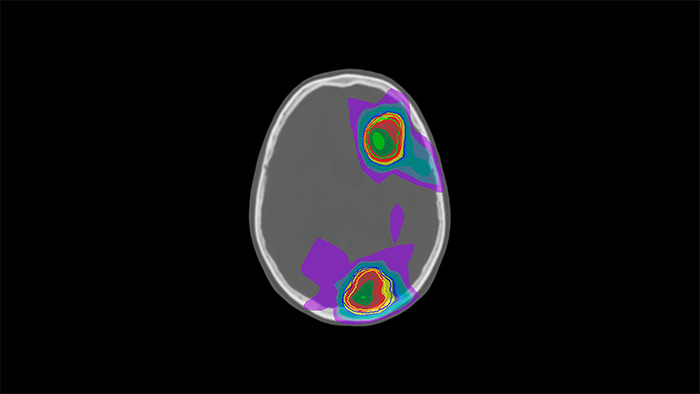

MRCAT Brain